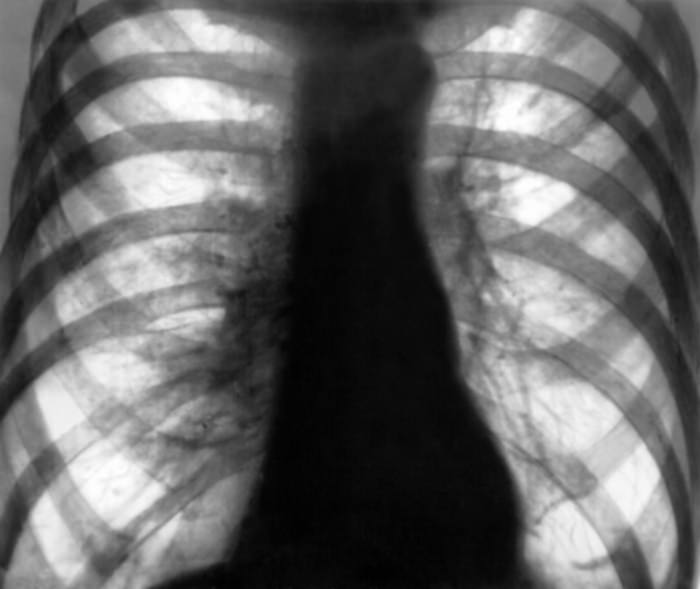

При вторичной эмфиземе происходят серьезные нарушения газового состава крови. Также при обоих видах эмфиземы уменьшаются дыхательные экскурсии, грудная клетка становится бочкообразной. Надключичные области выбухают, появляется перкуторный звук, уменьшается подвижность диафрагмы и ее расположение. На рентгенограмме видна повышенная прозрачность легочных полей.

Фотографии эмфиземы

В историях болезни можно обнаружить интересные рентгеновские снимки, наглядно демонстрирующие патологическую картину эмфиземы легких. Отчетливо видны буллы при буллезной форме — в виде светлых округлых полостей. Обеднение сосудистого рисунка, уплощение диафрагмы, прозрачные легочные поля типичны для диффузных форм эмфиземы.